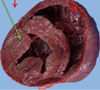

Pathogenesis (img)

Grain overload, rumenal acidosis, mucosal damage, opportunistic fungal infection, vasculitis, ischemia and mucosal ulceration